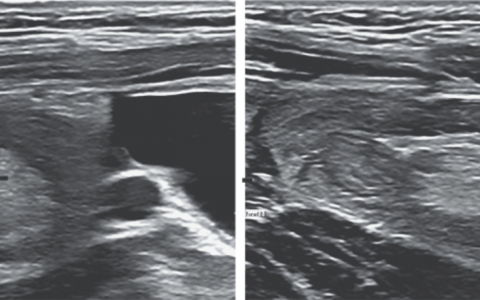

急性主动脉瓣关闭不全,无论是瓣周的还是中央的,都是经导管主动脉瓣置换术 (TAVR) 的已知并发症,据报道发生率高达70%。急性主动脉瓣返流导致收缩期左心室 (LV) 突然容量超负荷。因此,LV收缩末期容积高于正常,在随后的舒张期,左心房和 LV 之间的压力梯度降低较早。这导致早期二尖瓣关闭,可闻及软 S1 音。由于 LV 的心室-动脉梯度变化,观察到早期收缩甚至舒张二尖瓣返流。这导致 LV 每搏输出量减少和反射性心动过速。因此,患者常有脉搏细弱和四肢冰冷。

TAVR 术后曾观察到心包填塞,但较为罕见。此外,据报告,患者的颈静脉搏动在胸骨角上方 5 cm 处,再充盈缓慢,与填塞不一致。败血症与心动过速和低血压相关,但通常与四肢冰冷和体温正常无关。在 TAVR 术后报告了急性三度心脏传导阻滞,但通常与心率过快无关。房室传导完全丧失可引起心输出量下降和低血压,但通常心输出量减少的原因是心动过缓,而不是每搏输出量减少。此外,通常不会观察到舒张期杂音。升主动脉夹层是一种罕见但已知的并发症,肯定比主动脉瓣关闭不全少见。但这应伴有冠状动脉缺血。与急性二尖瓣反流相关的典型杂音是高调、吹风样全收缩期杂音。